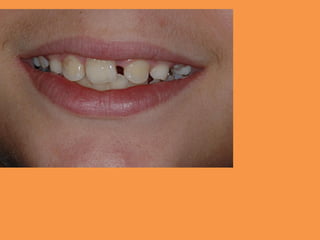

Figure 3: Panoramic radiograph

showing mild eruption of 11

Figure 3: Panoramicradiograph showing mild eruption of 11